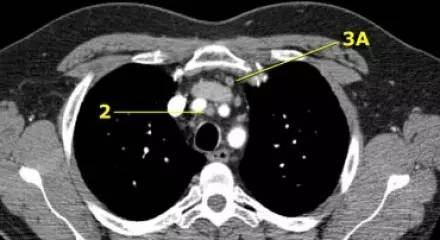

肺 CT 横断面上的上气管旁淋巴结(2)和血管前淋巴结(3A)